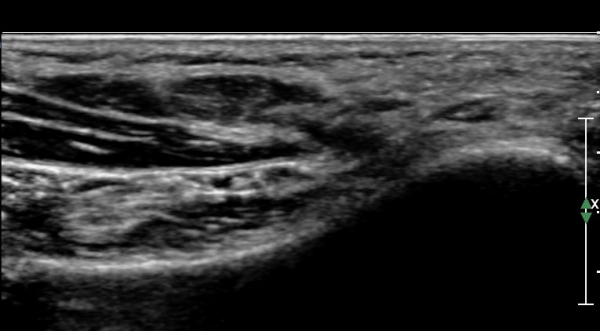

ŽÃËÀÚ¸¦ Á¶±Ý ´õ ¹ß¹Ù´ÚÃøÀ¸·Î À̵¿ÇÏ´Ï ¾Æ·¡µÚ²ÞÄ¡½Å°æÀÌ Àú¿¡ÄÚ µ¢¾î¸® ¸ð¾çÀ¸·Î °üÂûµÈ´Ù

(»çÁø 3, 4)